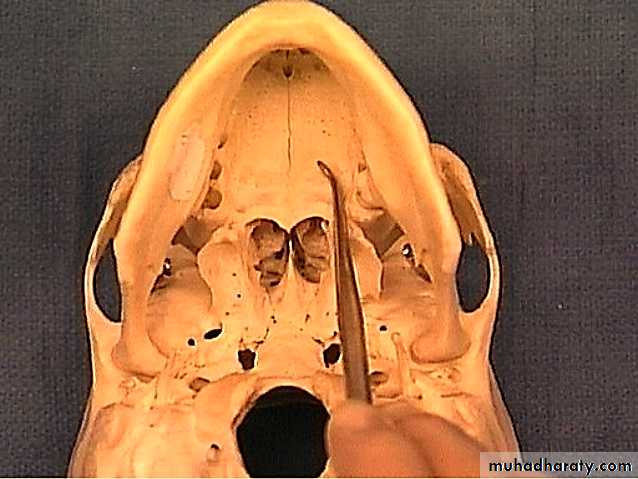

Surface Anatomy of Hard palate

In the midline; at the front of the hard palate lies the incisive fossa, posterior to the central incisor teeth into which the incisive canals open

Medial to the 3rd molar tooth, the greater palatine foramen pierces the lateral border of the bony palate.

The greater palatine vessels and nerve emerge from this foramen and run anteriorly on the palate.

The lesser palatine foramina lie posterior to the greater palatine foramen.